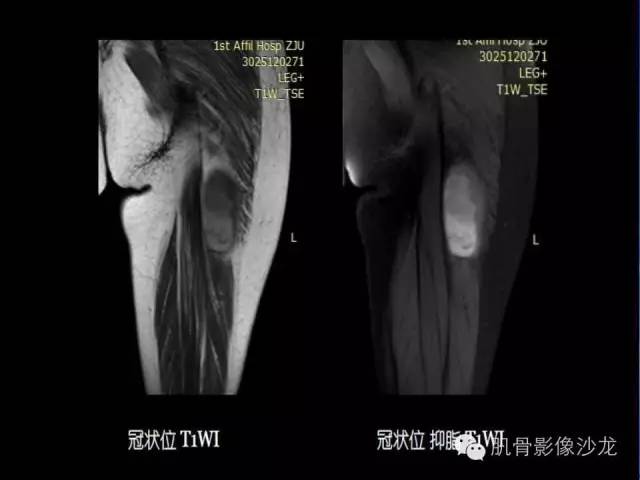

【病例】恶性外周神经鞘膜瘤1例MR影像表现